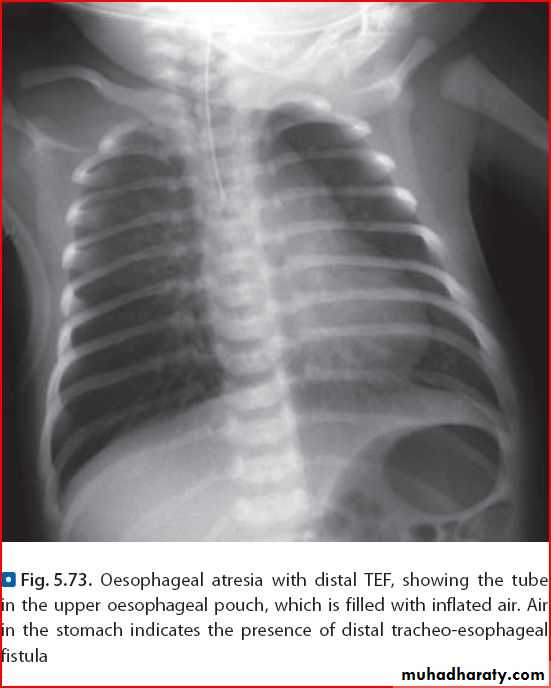

Esoph. atresia

Esophagial atresia or achalasia ???